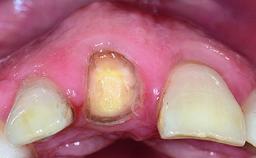

Replacement of a Failing Upper Left Central Incisor: Immediate Placement of an RC Bone Level Implant and Provisionalization

Abutment Type CAD/CAM

Prosthesis Type FDP